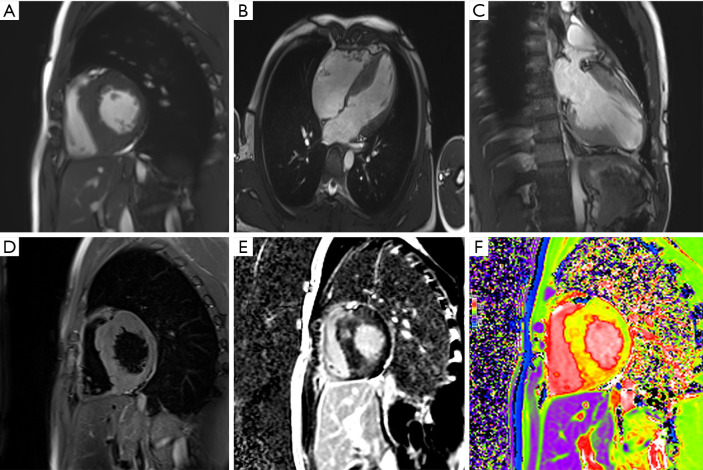

背景与目的:放射组学是一项新兴技术,有助于心脏多模态磁共振成像(MRI)的定量分析。本研究旨在引入放射组学在非缺血性心肌病中应用的标准化工作流程,使临床医生能够在临床实践中全面理解和应用该技术。方法:计算机化检索PubMed文献(截止到2024年8月1日),确定放射组学在非缺血性心肌病中的作用和工作流程的相关研究。还举行了专家讨论,以确保调查结果的准确性和相关性。只审查了英文出版物。主要内容和发现:本文详细介绍了放射组学的基本过程,包括特征提取、特征工程、模型构建和数据分析。它强调了MRI在评估心脏结构和功能中的作用,并展示了基于MRI的放射组学如何帮助诊断和区分非缺血性心肌病,如肥厚性心肌病、扩张性心肌病和心肌炎。本研究还探讨了各种心脏MRI序列,以加强放射组学的临床应用。结论:本研究提出的标准化放射组学工作流程旨在帮助临床医生有效地利用基于mri的放射组学进行非缺血性心肌病的诊断和管理,从而改善临床决策。

Key content and findings: The paper details the essential processes of radiomics, including feature extraction, feature engineering, model construction, and data analysis. It emphasizes the role of MRI in assessing cardiac structure and function and demonstrates how MRI-based radiomics can aid in diagnosing and differentiating non-ischemic cardiomyopathies such as hypertrophic cardiomyopathy, dilated cardiomyopathy, and myocarditis. The study also investigates various cardiac MRI sequences to enhance the clinical application of radiomics.